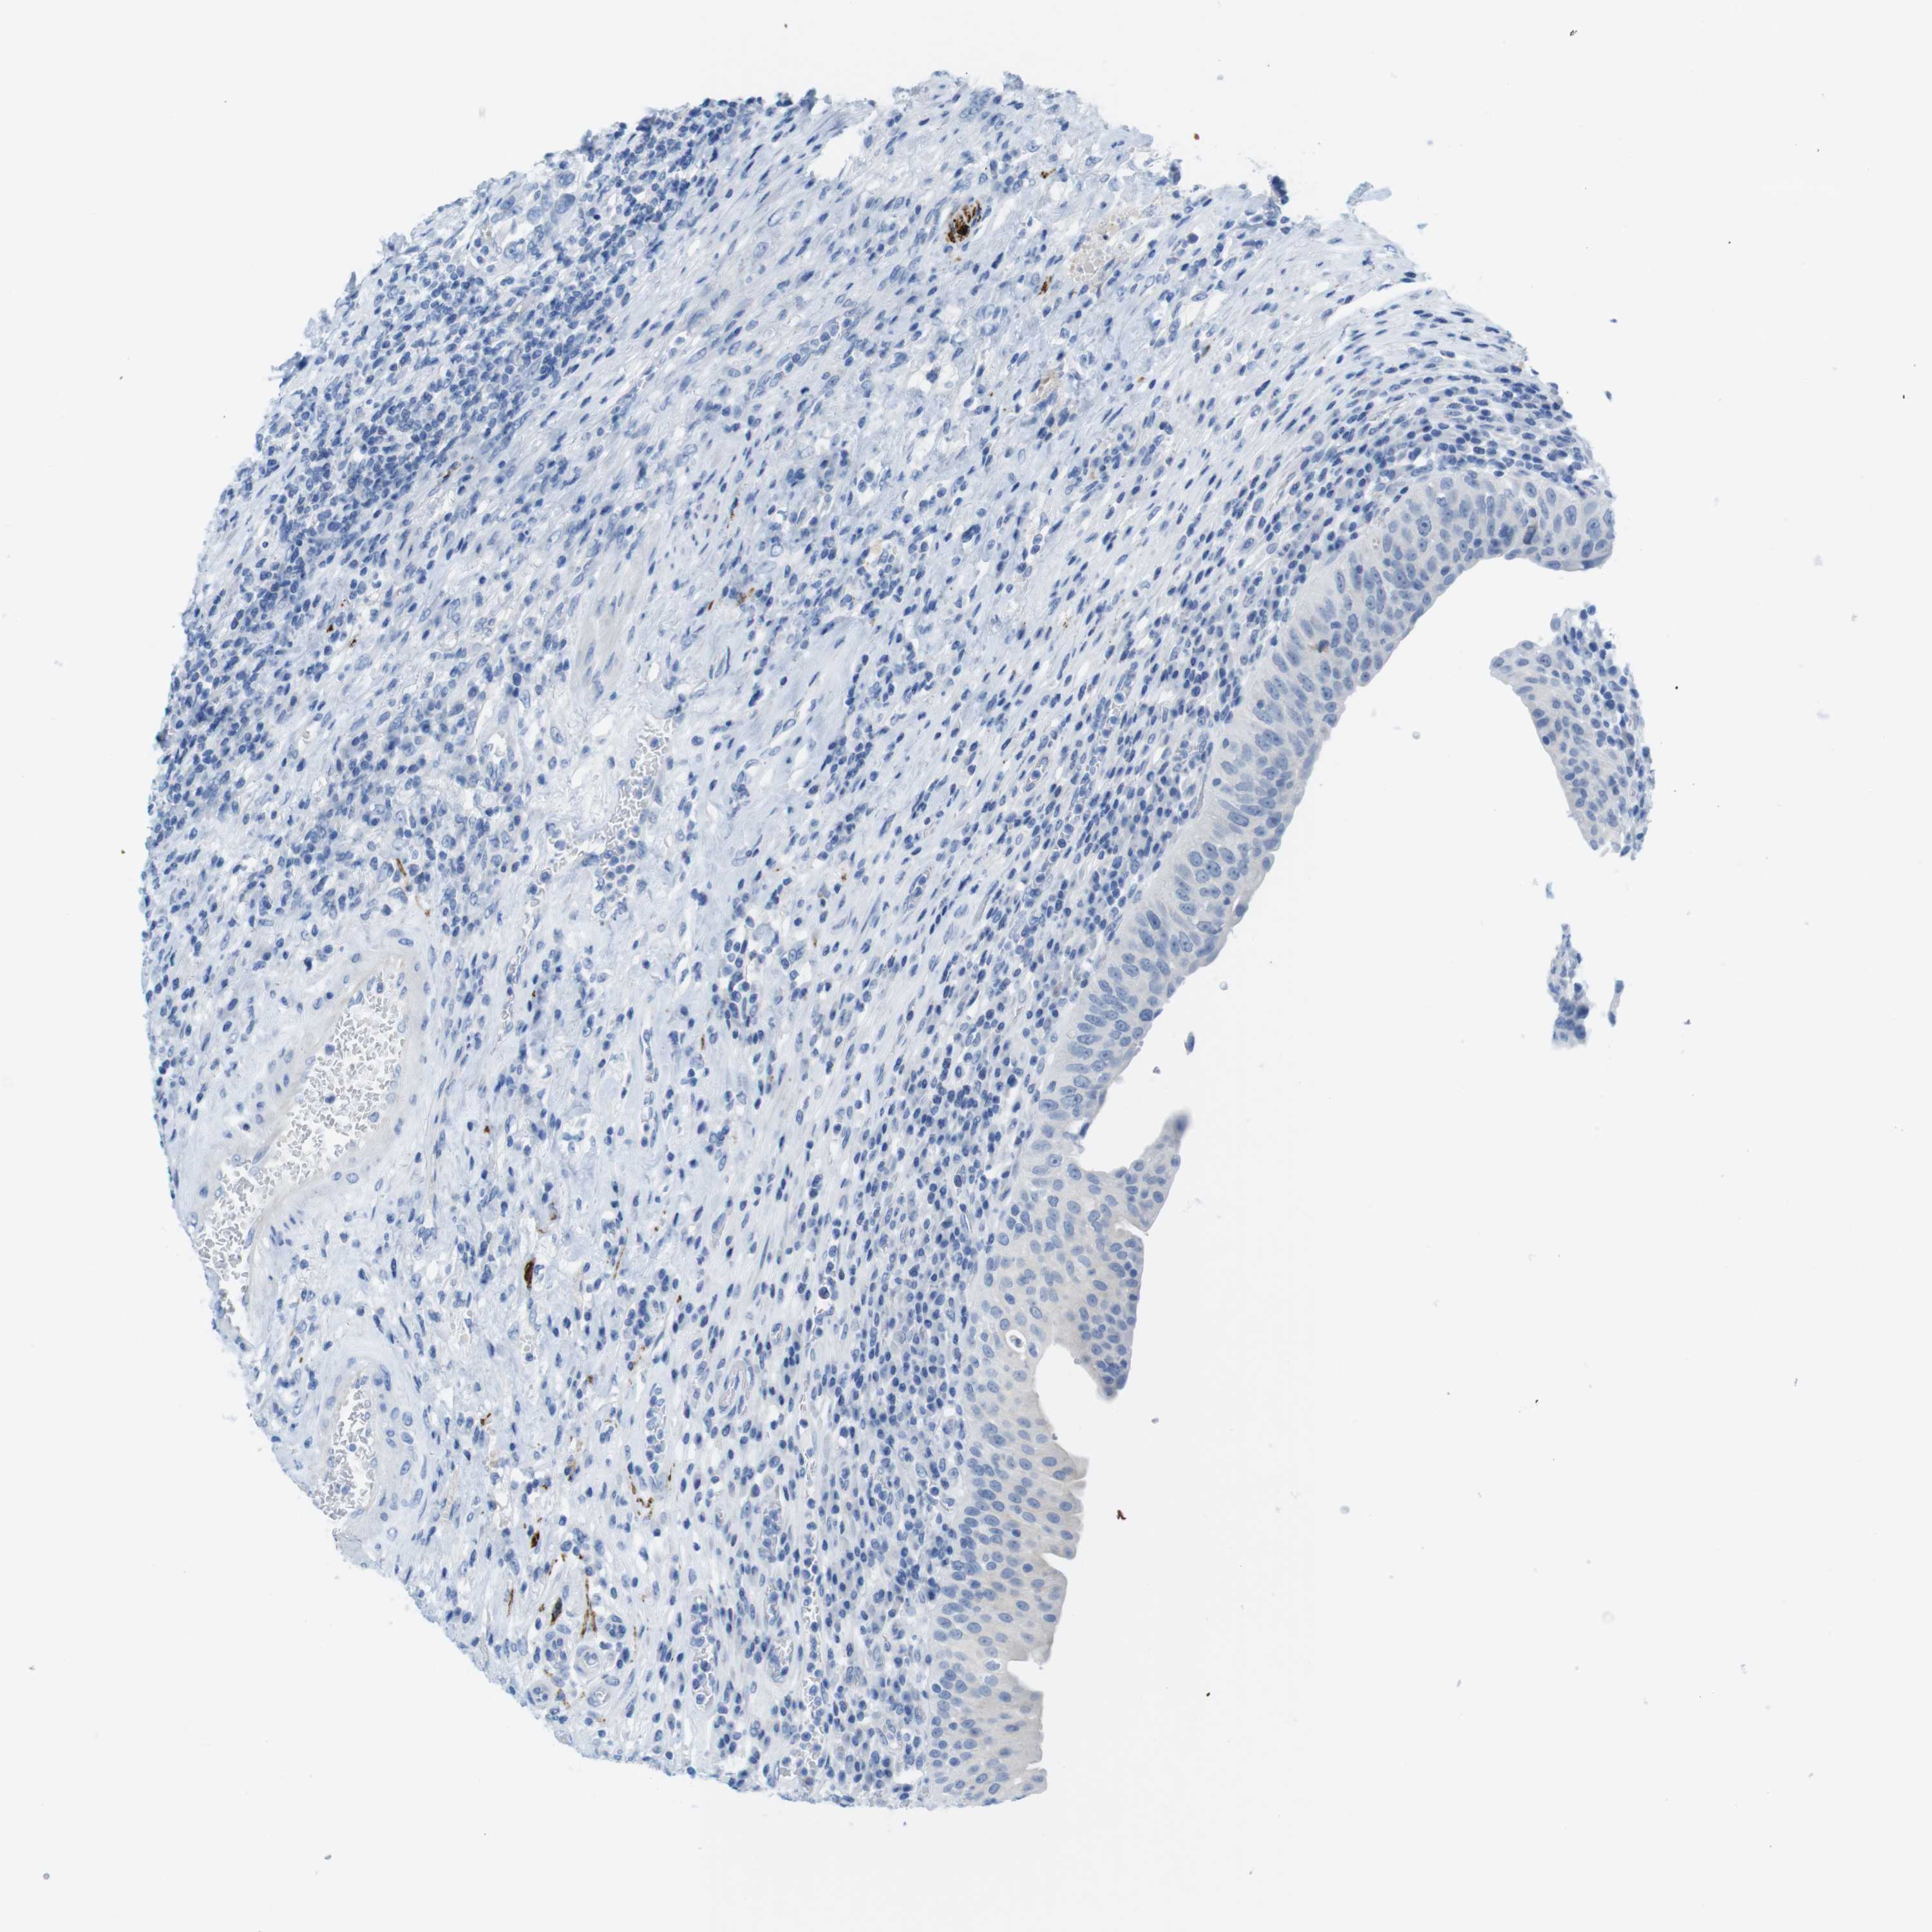

UROTHELIAL CANCER - Protein expressioni

A mouse-over function shows sample information and annotation data. Click on an image to view it in a full screen mode. Samples can be filtered based on level of antibody staining by selecting one or several of the following categories: high, medium, low and not detected. The assay and annotation is described here.

Note that samples used for immunohistochemistry by the Human Protein Atlas do not correspond to samples in the TCGA dataset.

Antibody stainingi

Antibody staining in the annotated cell types in the current human tissue is reported as not detected, low, medium, or high, based on conventional immunohistochemistry profiling in selected tissues. This score is based on the combination of the staining intensity and fraction of stained cells.

Each image is clickable and will lead to virtual microscopy that enables deeper exploration of all samples and also displays staining intensity scores, fraction scores and subcellular localization as well as patient and tissue information for each sample.

Antibody HPA013392

Antibody HPA015600

Antibody CAB004417

Staining

High

Medium

Low

Not detected

Intensity

Strong

Moderate

Weak

Negative

Quantity

>75%

75%-25%

<25%

None

Location

Nuclear

Cytoplasmic/membranous

Cytoplasmic/membranous,nuclear

Urothelial carcinoma, Low grade

Urothelial carcinoma, High grade